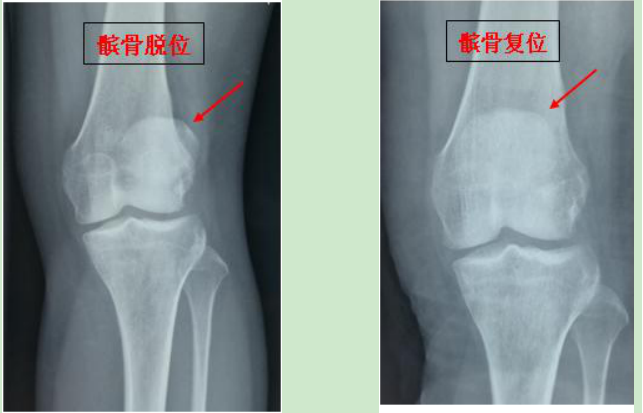

髌骨脱位_骨折_疾病网

髌骨脱位怎么办?

而髌骨脱位是不可以都归为一类,它主要的情况可以分为三种:多发于儿童的习惯性髌骨脱位、慢性复发性髌骨脱位和急性创伤性髌骨脱位。髌骨脱位具体又是怎么样的呢?它是